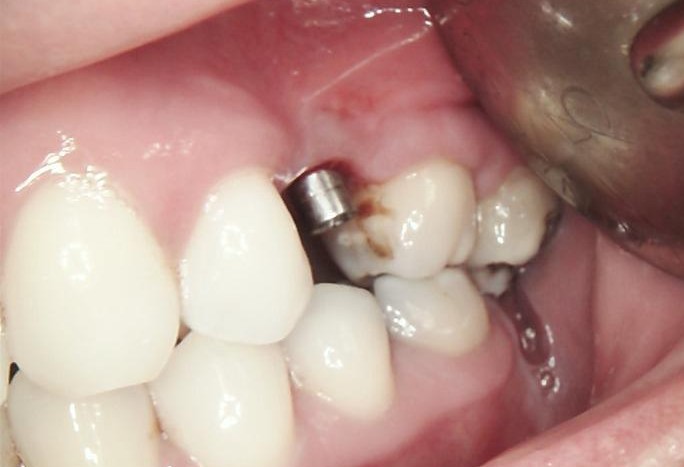

INITIAL STATE

Clinical and radiographic examination revealed a failed implant with signs of periimplant tissue compromise. Intraoral evaluation demonstrated inadequate soft tissue quality and unfavourable conditions for immediate restoration. CBCT imaging was performed to assess bone volume, implant position, and anatomical limitations prior to treatment planning.